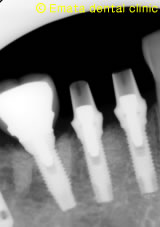

レントゲンでもインプラントのまわりの骨も安定しています。